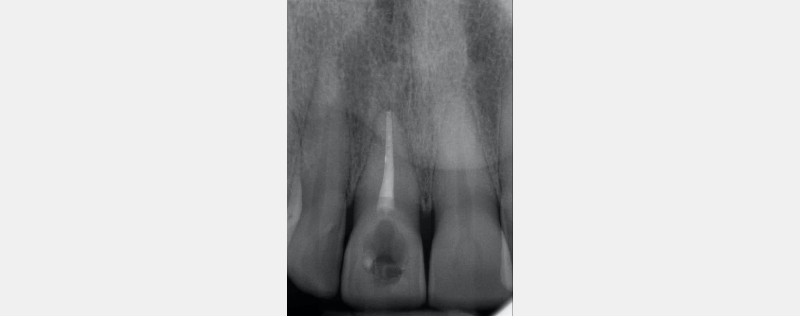

- The RMGIC coronal barrier seal is placed. The position is verified with a periapical radiograph. This is important for both clinical and medico-legal reasons.